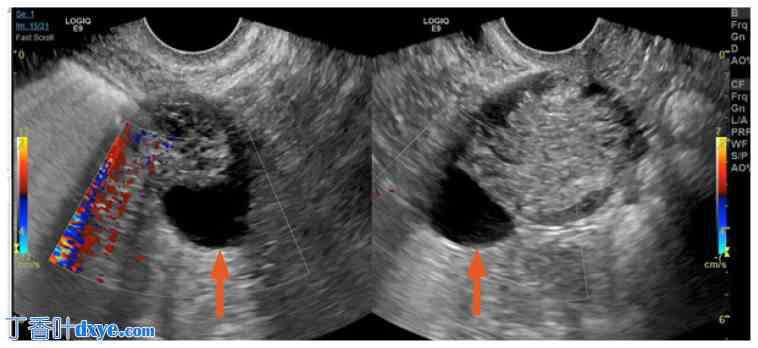

经阴道超声检查显示子宫已被切除。右侧卵巢未见显影。左侧卵巢尺寸为4.4 x 3.7 x 5.0厘米。检测到左侧卵巢静脉血流,但难以获得动脉血流。左侧卵巢囊肿较小,大小为 2.2 x 1.9 x 2.2 厘米,形态简单。左侧卵巢中央可见一回声区,大小为 3.6 x 2.8 x 3.0 厘米。未见附件肿块或盆腔积液。膀胱未见异常(图 1 和图 2)。

经阴道彩色多普勒超声检查左卵巢,显示卵巢囊肿(箭头)。